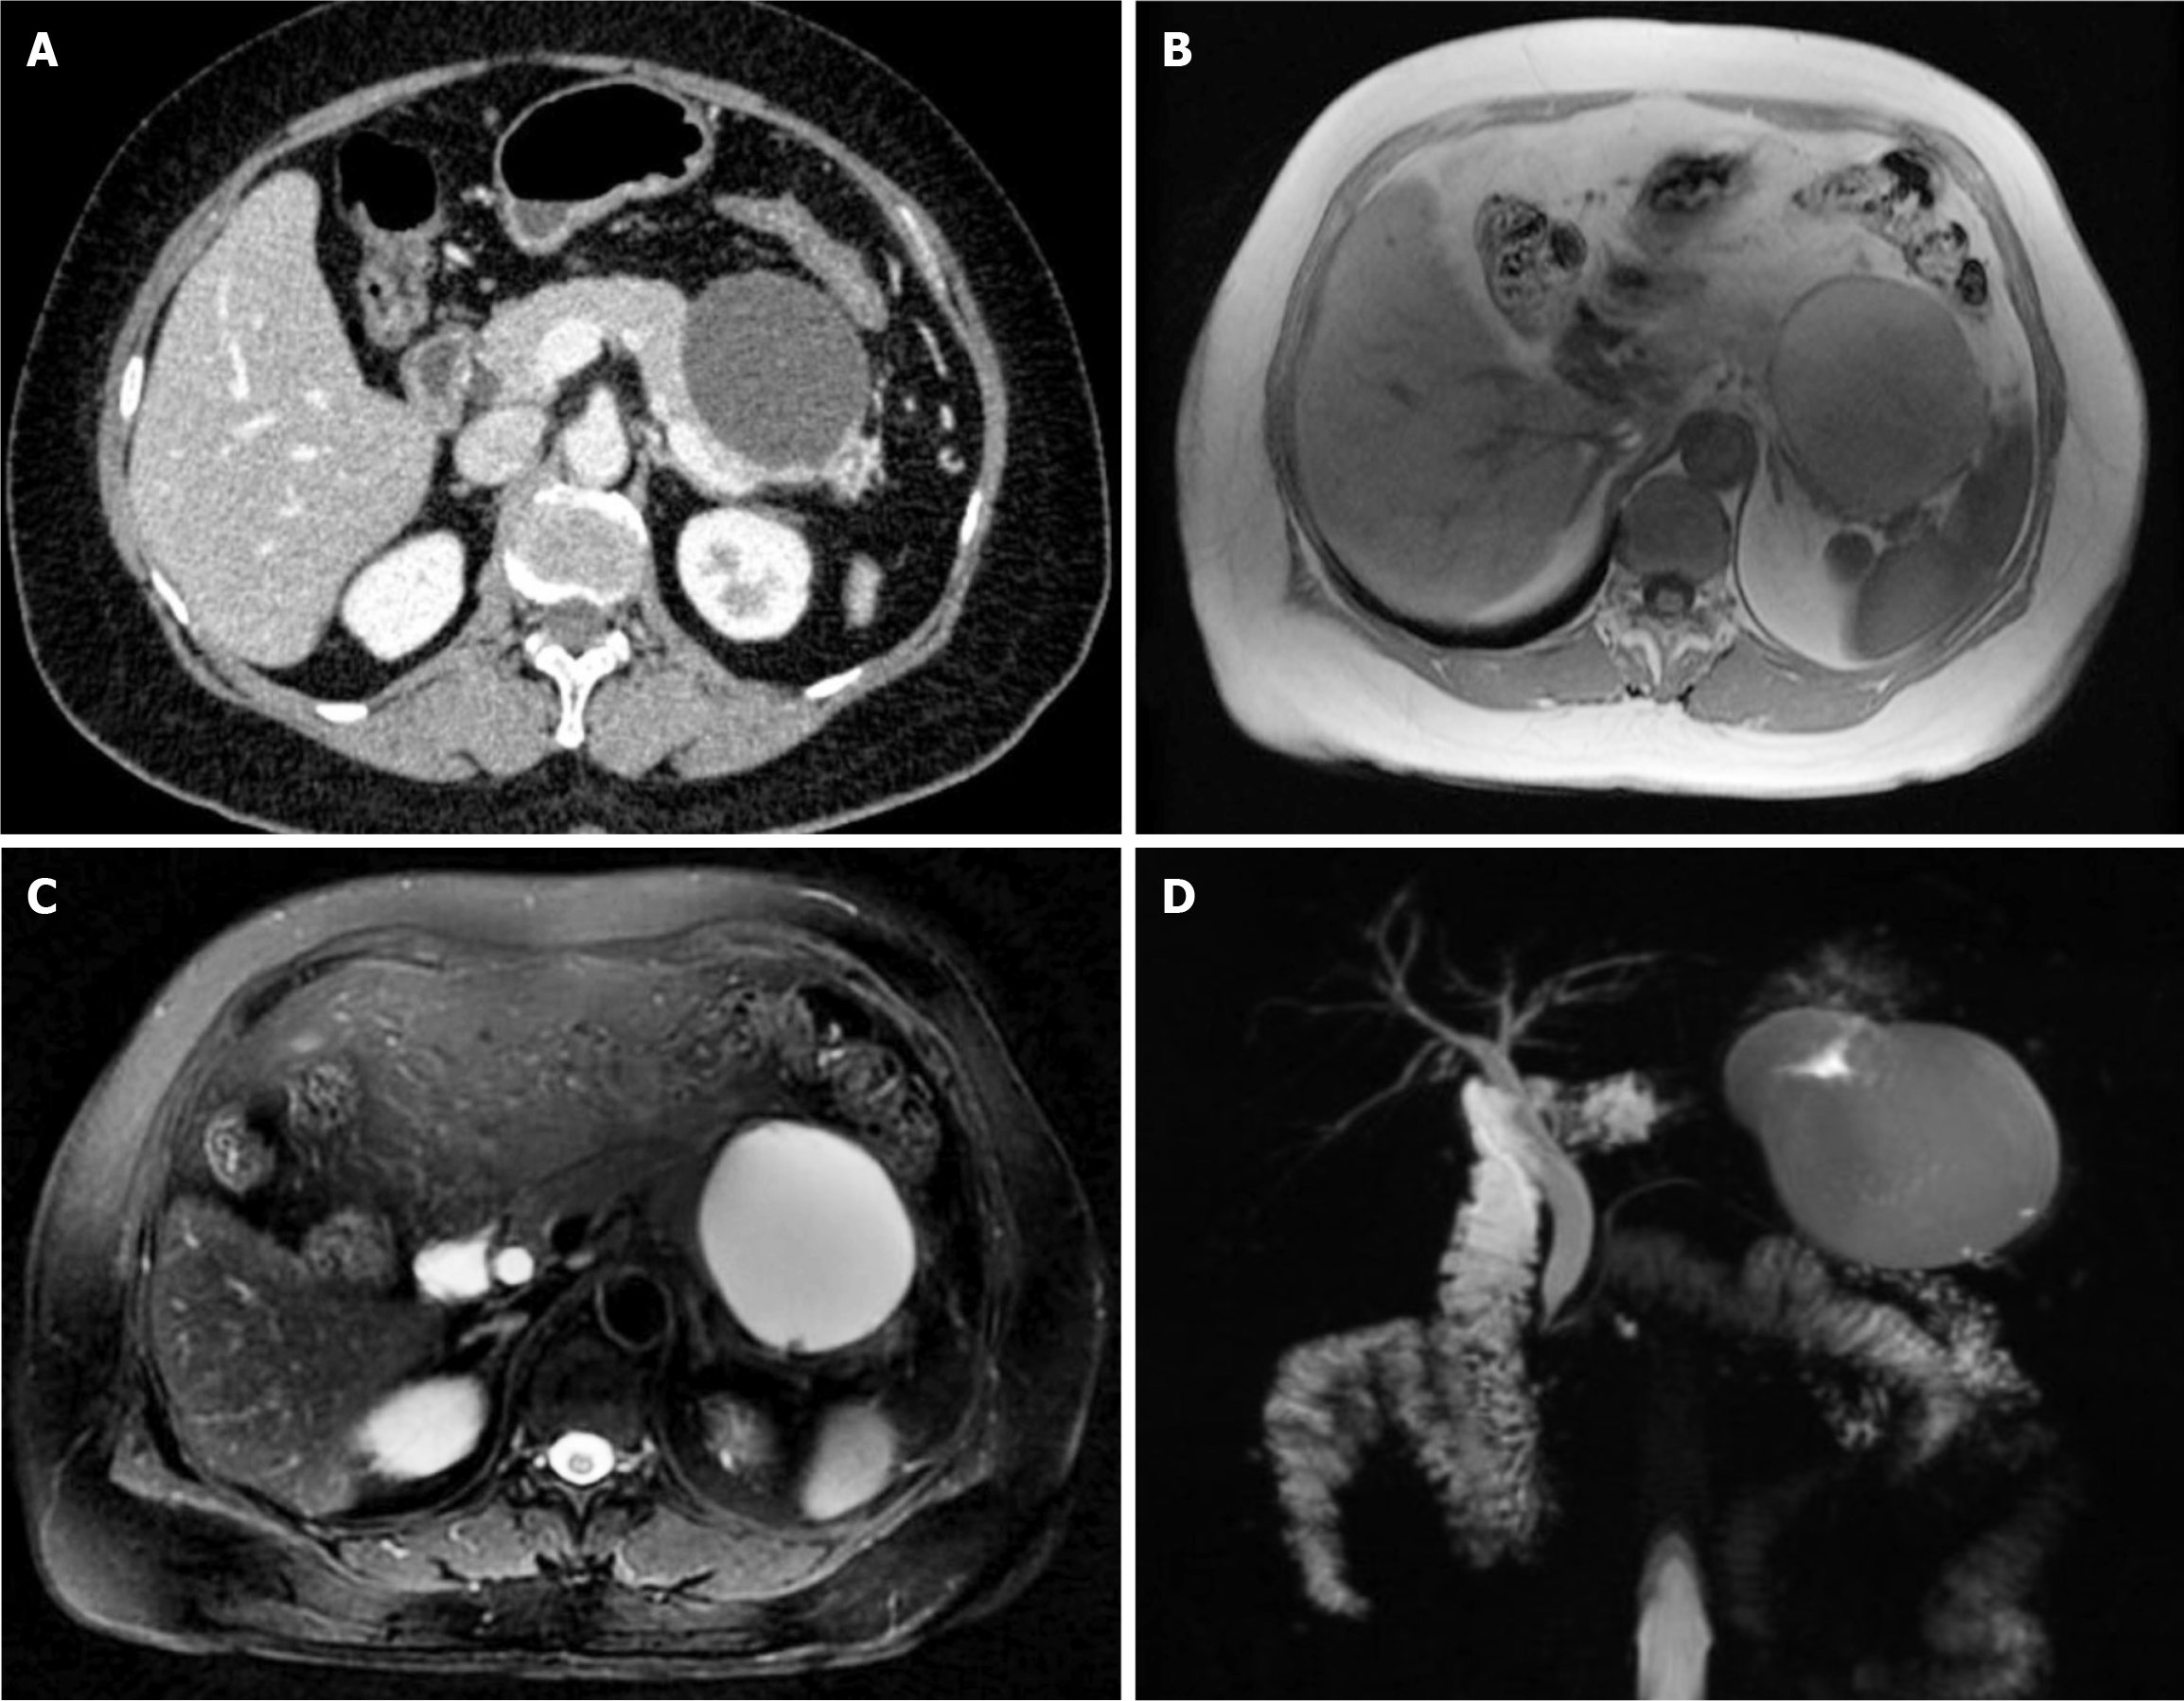

Figure 1 Initial imaging showing the cystic mass located in the tail of the pancreas and pushing against the stomach wall.

A: Abdominal contrast-enhanced computed tomography scan; B and C: Magnetic resonance imaging; D: Magnetic resonance cholangiopancreatography.